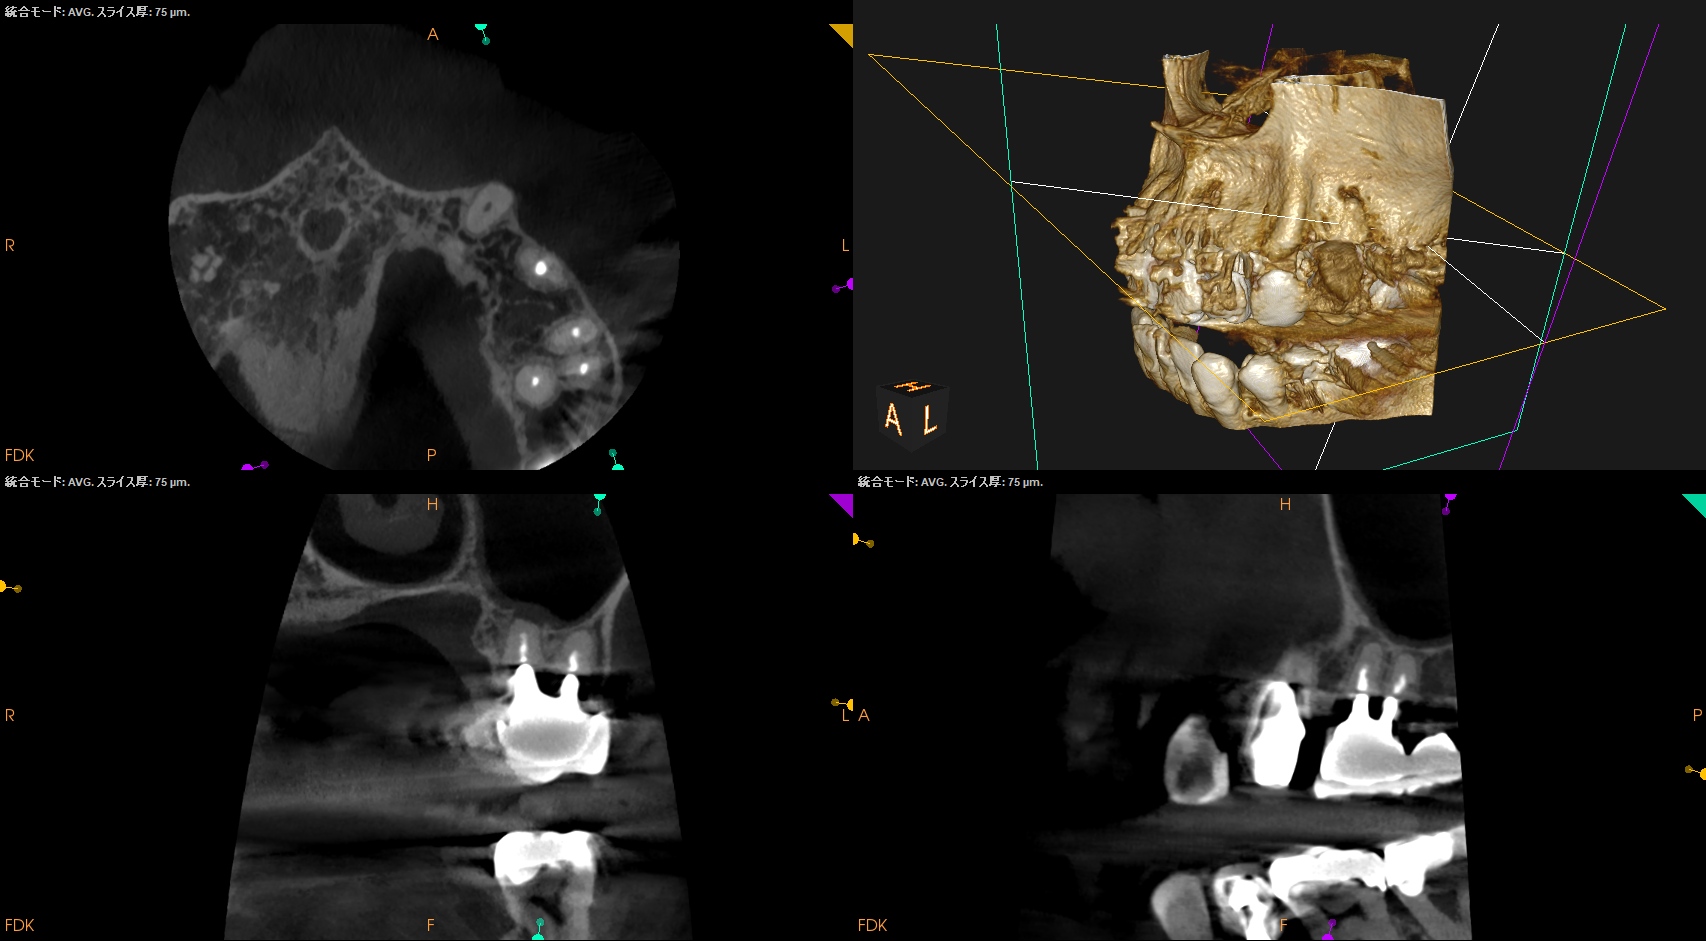

CBCT(2024.7.1)

#3

MB

DB

P

MB,DB,Pと3根全てに病変がある。

しかも形成が不完全だ。

再根管治療が濃厚である。

#14

MB,DBには病変がないが、Pに存在する。

これは頭が痛い。

パラタルフラップも困難なケースだからだ。

#16